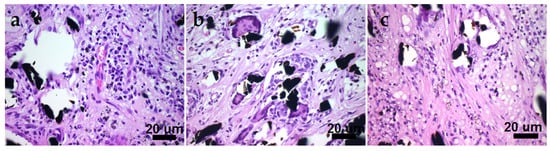

On the outside of all the samples, FCs were formed by classic loose connective tissues and structurally identical in terms of relative location and the thickness of individual fibers. Inside the samples, FC fibers formed a cell-filled fibrous base with a predominance of collagen. The host organism formed an insulating capsule around each fiber. In addition to the cells usual for loose connective tissue, macrophages, “foreign body” cells (FBCs) and lymphocytes were present in all the studied samples (Table 3). The histological differences between the samples were in the number of cells of each type and the density of collagen fibers (Figure 13).

Figure 13. CCM sample micrographs demonstrating a large number of FBCs, macrophages, and lymphocytic cells ((a)—Pt/CCM sample, (b)—Ag/CCM sample, (c)—Au/Pt/CCM sample). The black inclusions are carbon fibers.